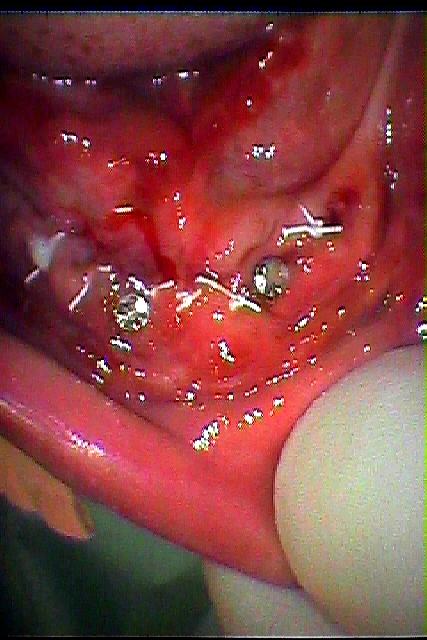

お知らせ|広島市安佐南区の歯科医院 > お知らせ トップ お知らせ・ブログ お知らせ スタッフブログ お知らせ お知らせ 2024/09/24 下前歯のインプラントを用いたパーシャルデンチャーケースになります お知らせ 2024/09/24 下顎の前歯部がグラグラする 診てほしい 無歯顎のインプラントを用いたパーシャルデンチャー お知らせ 2024/09/21 前歯のブリッジが大きく動きだしてきた診てほしい 前歯部のインプラント埋入の臨床現場 お知らせ 2024/09/21 右上2番欠損のジルコニアブリッジの臨床現場 お知らせ 2024/09/20 左下の6番部のインプラント埋入 2本ケース 上部構造はセラミックにて仕上げていきます お知らせ 2024/09/20 左下のブリッジが食事をしていたら取れた 診てほしい インプラント治療の臨床現場 お知らせ 2024/09/18 左下の4番部のセラミックによる審美治療 インレー形態をとります お知らせ 2024/09/18 右下の4番部 セラミック希望にて審美修復治療 お知らせ 2024/09/17 左上の大臼歯部の親不知の水平埋伏歯の難抜歯 虫歯になっていました お知らせ 2024/09/17 右下の親不知の水平埋伏気味の歯を抜歯していきます 30代男性 << 1 2 3 4 5 … 24 25 26 27 28 … 485 486 487 488 489 >> Web診療予約 初めての方へ 選ばれ続ける理由 院内設備について 歯が痛いしみる一般歯科 歯がぐらぐらする歯周病 健康な歯を保ちたい予防歯科 子供の虫歯予防をしたい小児歯科 銀歯をセラミックに審美歯科 白い歯を目指しませんか?ホワイトニング 矯正専門医がいるので安心矯正歯科 抜けた歯を補いたいインプラント・入れ歯 医院案内 スタッフ紹介 メリィハウス歯科クリニックオフィシャルホームページ ラベンダー歯科クリニックオフィシャルホームページ お知らせ・ブログ ホーム 診療科目 一般歯科 歯周病治療 予防治療 小児歯科 審美治療 ホワイトニング 矯正歯科 入れ歯・インプラント マウスピース矯正 初めての方へ 院長・スタッフ 設備紹介 医院案内・アクセス メニューを閉じる